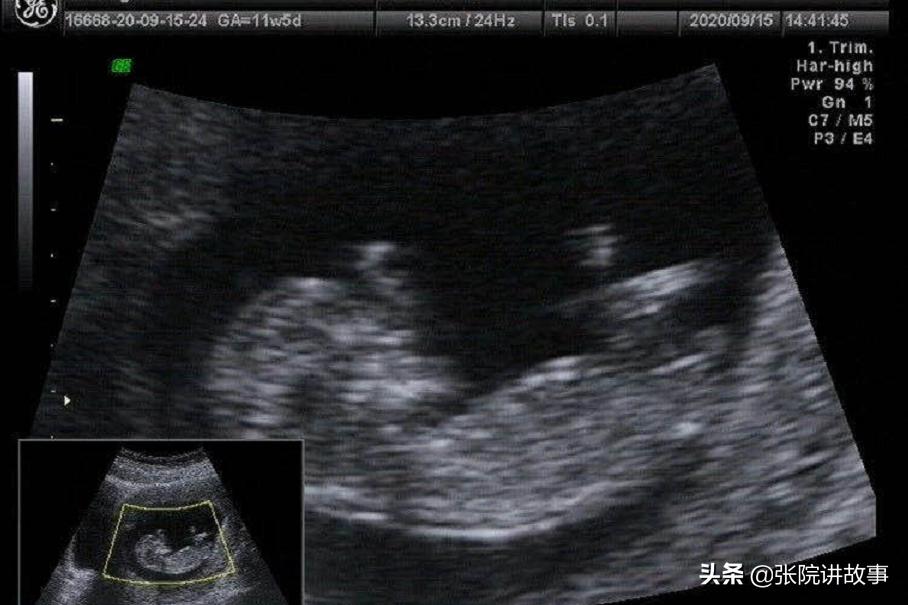

欧阳医生在检查的时候,就发现阴道里面有一个鹌鹑蛋大小的子宫肌瘤从宫腔里头脱出来,有一个蒂部延伸到宫腔里面,宫颈就被肌瘤扩张、牵拉变薄了。肌瘤因为它长时间的脱出,表面已经水肿,颜色已经发黑。从B超上也看到它整个子宫体积是增大的,子宫肌壁间还可以看到很多大小不同的这种肌瘤结节,比较大的都有19×17mm左右,宫腔线也是分离的,而宫颈的那一部分还可以看到34×26mm左右的一个低回声的结节。